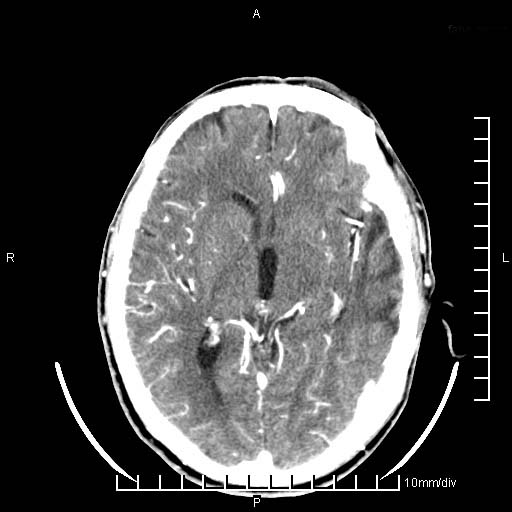

临床以双下肢浮肿,疼痛收治,无明显神经系统症状,既往无梗塞,出血病史。左颞叶见低密度灶,考虑什么?

考虑左侧颞叶脑软化灶。

无强化 无占位 软化灶吧

无强化、 无占位、局部脑沟增宽, 软化灶吧。